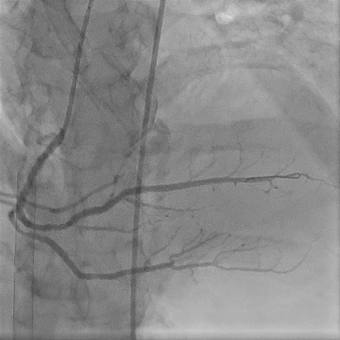

В рентгеноперационной после выполнения коронарографии выявлен тромбоз крупной правой коронарной артерии с полным прекращением кровотока. Рентгенэндоваскулярный хирург произвел реканализацию тромбированного участка с аспирационным удалением тромба и стентированием правой коронарной артерии.

После восстановления кровотока по правой коронарной артерии состояние пациента стабилизировалось. Удалось снизить дозы медикаментозной поддержки. В течение 24 часов с целью профилактики постреанимационного отека головного проводилась искусственная гипотермия до 35°С. Через 50 часов после развития фатального осложнения инфаркта миокарда пациент пришел в сознание, был экстубирован. Производительность контура ЭКМО постепенно снижали, на шестые сутки пациент был отключен от системы ЭКМО, еще через день был переведен в отделение кардиологии и в последующем выписан. Перед выпиской отмечал хорошее самочувствие, сократительная способность сердца практически не пострадала. После реабилитации пациент сможет вернуться к обычной жизни.